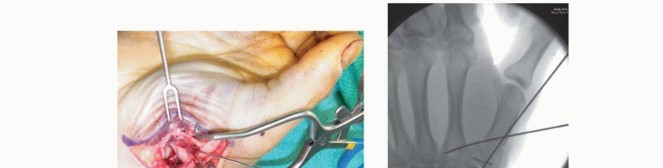

CRPP is the treatment of choice for classic Bennett fractures where the volar-ulnar fragment is too small to reliably accept a lag screw, yet the joint can be anatomically reduced closed. The reduction maneuver is highly specific, designed to counteract the deforming forces of the APL and Adductor Pollicis. Longitudinal traction is applied to the thumb, followed by palmar abduction and pronation. Direct pressure is then applied to the dorsal-radial aspect of the metacarpal base, effectively pushing the shaft back into the anatomic cradle of the intact volar-ulnar fragment.

Once anatomic reduction is confirmed via multi-planar fluoroscopy, percutaneous fixation is achieved. Typically, two 0.045-inch or 0.062-inch Kirschner wires are utilized. The first wire is driven from the dorsal-radial aspect of the metacarpal shaft directly into the trapezium, effectively neutralizing the proximal pull of the APL. A second wire is often placed transversely from the first metacarpal shaft into the second metacarpal to control rotation and maintain the web space. Pins are cut outside the skin and capped to facilitate easy removal in the clinic.

Open Reduction and Internal Fixation (ORIF) - Wagner Approach

For fractures with large volar-ulnar fragments (>20% of the articular surface), displaced Rolando fractures, or cases where closed reduction fails, ORIF is unequivocally mandated. The classic Wagner approach provides unparalleled exposure to the thumb CMC joint. A curvilinear incision is made along the glabrous border of the thenar eminence, curving dorsally at the level of the CMC joint.

Meticulous superficial dissection is required to identify and protect the sensory branches of the superficial radial nerve dorsally and the palmar cutaneous branch of the median nerve volarly. The thenar musculature (abductor pollicis brevis and opponens pollicis) is sharply elevated from the metacarpal shaft and retracted volarly. The joint capsule is then incised longitudinally or in an L-shaped fashion to expose the articular surface. The hematoma is evacuated, and the fracture fragments are meticulously debrided of interposed soft tissue.

For a large fragment Bennett fracture, the shaft is reduced to the volar-ulnar fragment using a pointed reduction clamp. Provisional fixation is achieved with a K-wire. A 1.5mm or 2.0mm lag screw is then placed perpendicular to the fracture plane. The near cortex must be overdrilled (gliding hole) and the far cortex underdrilled (thread hole) to achieve true interfragmentary compression. The screw head should be countersunk to prevent hardware prominence beneath the thenar muscles.